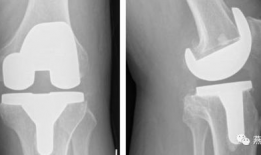

膝关节置换手术视频,从术前准备到术后康复

你有没有想过,当你的膝关节像老化的弹簧一样“嘎吱嘎吱”作响时,会有一种神奇的手术能把它换成一个全新的呢?没错,就是膝关节置换手术...